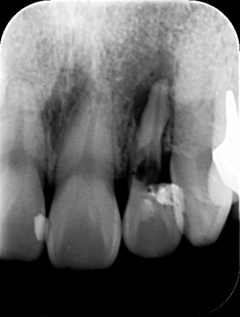

●大きく削ってインレーを詰めても細菌の取り残しがある→数年後、虫歯の再発

●大きく削ることで、別の痛みが引き起こされる場合がある

●削った部分がむき出しのまま、うがいをさせる。唾液で汚染される→さらなる虫歯や神経の炎症を起こす